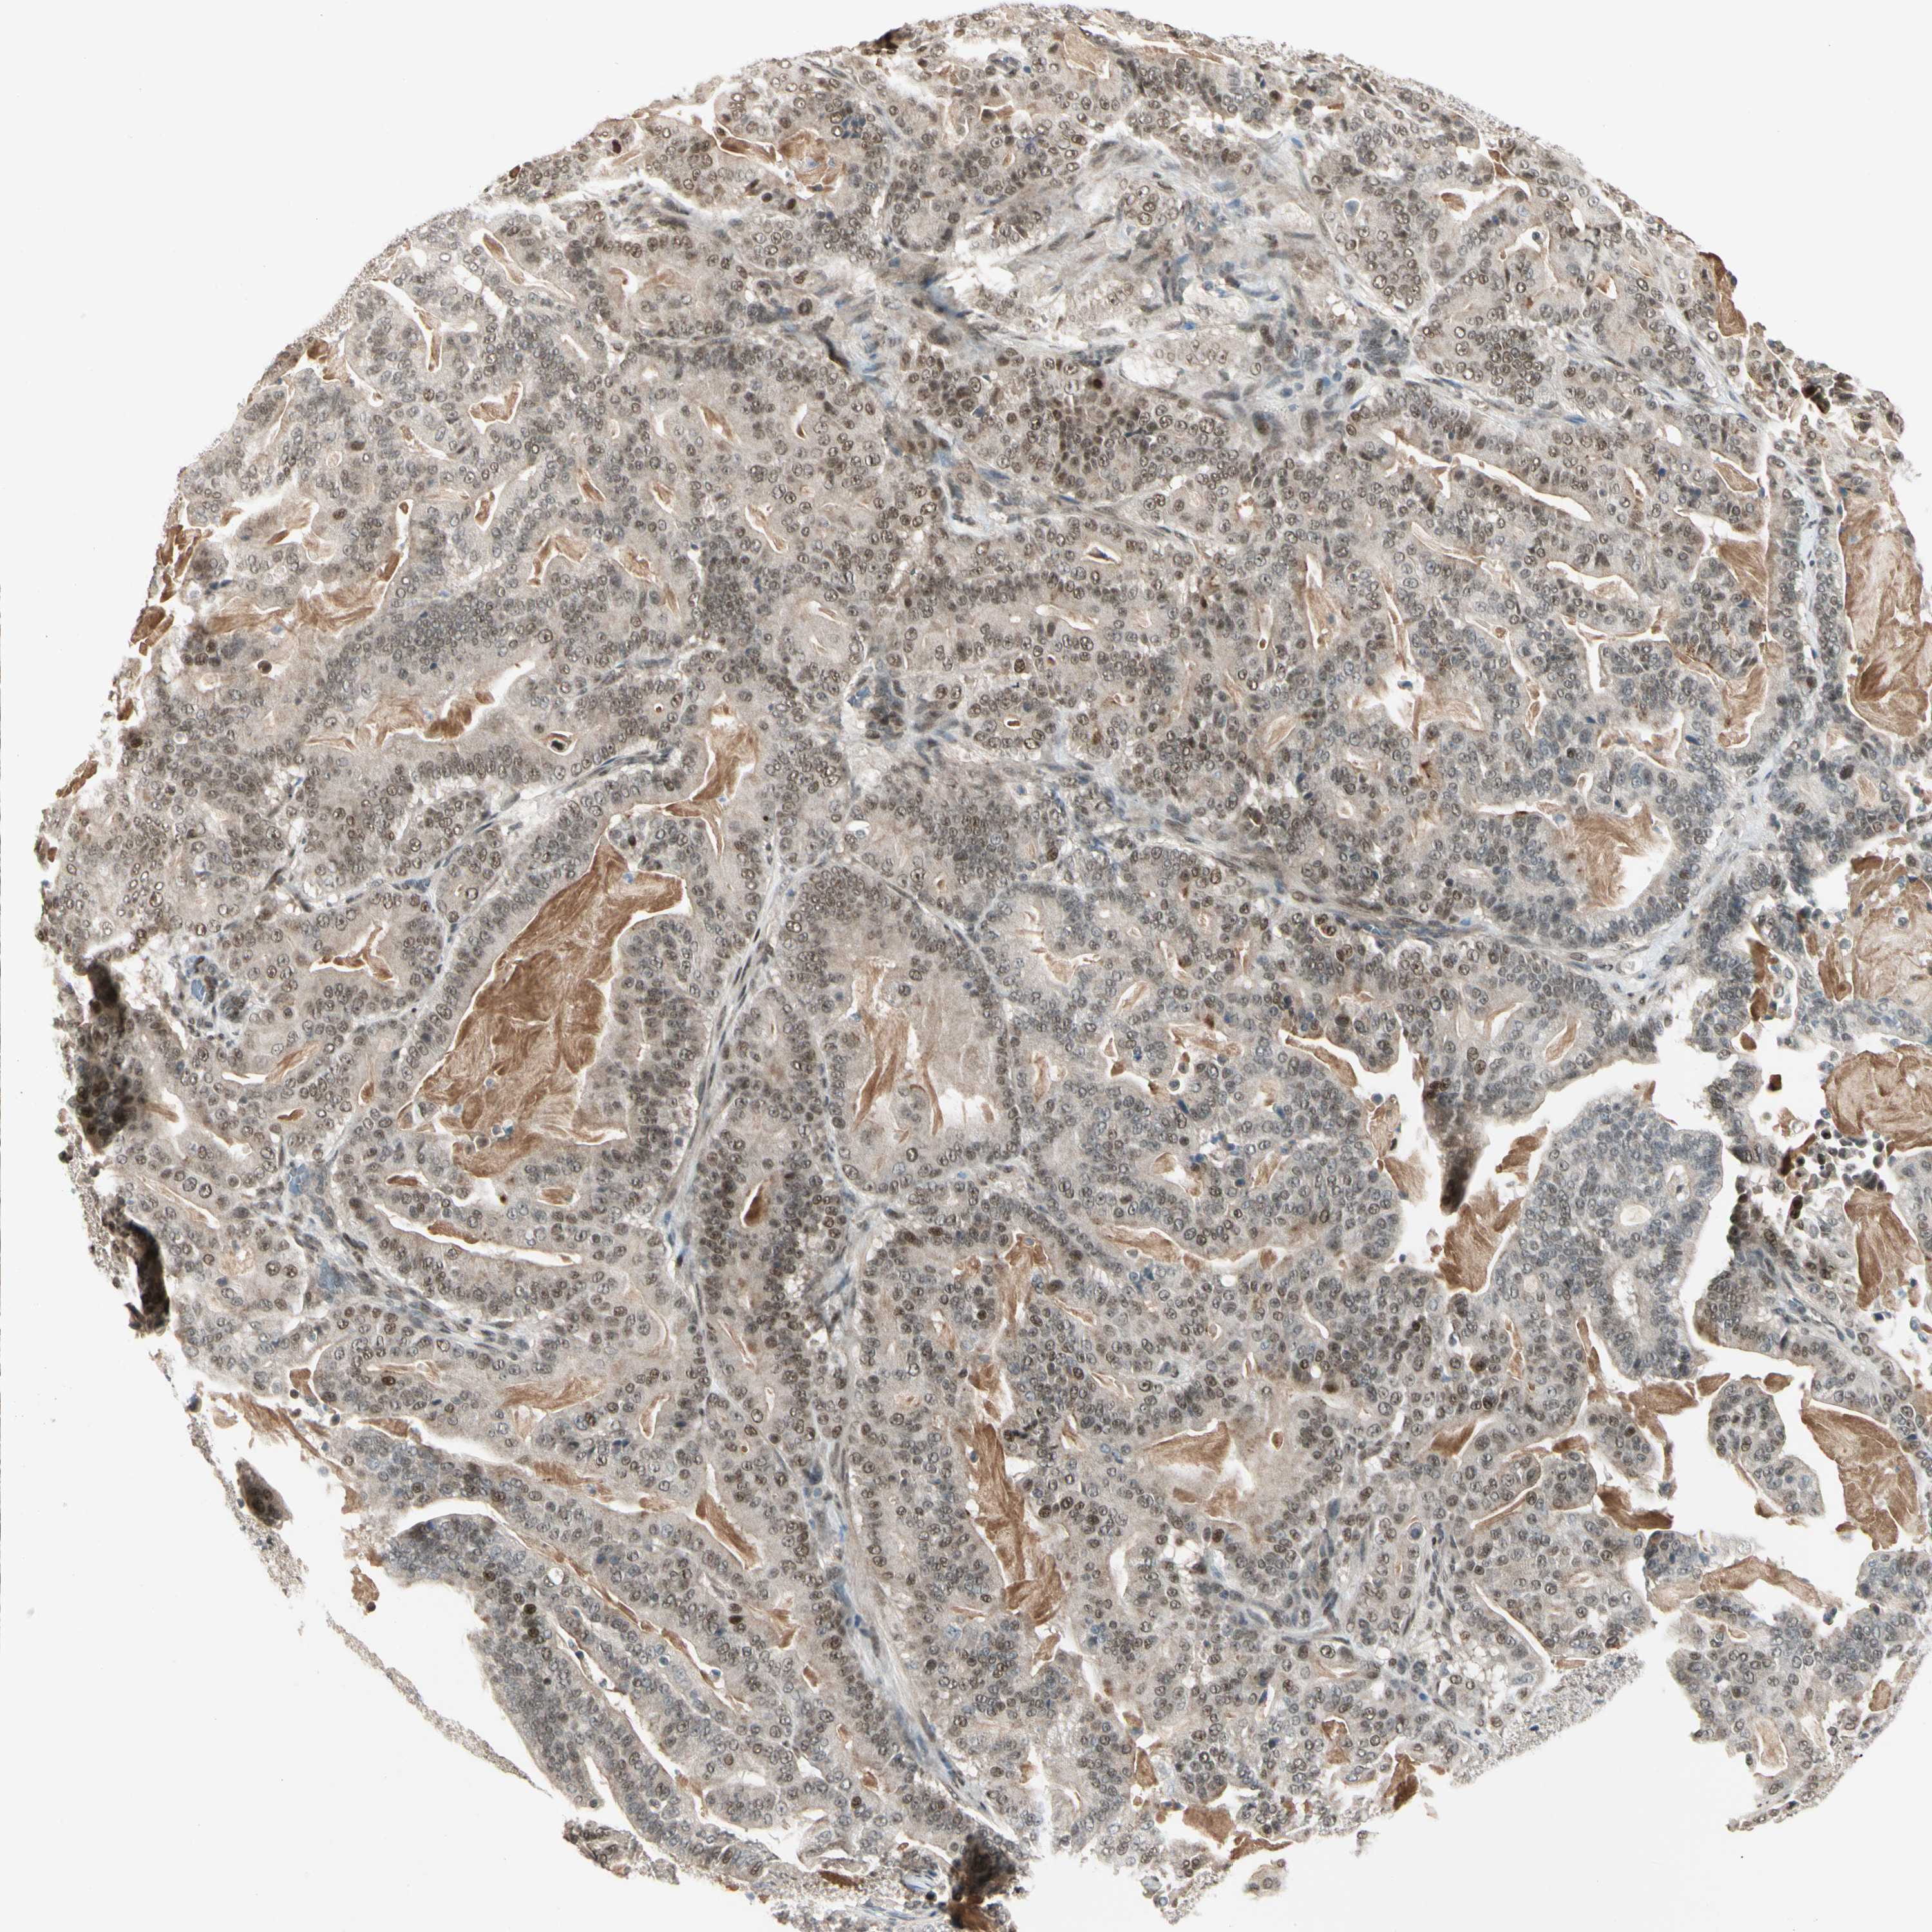

PANCREATIC CANCER - Protein expressioni

A mouse-over function shows sample information and annotation data. Click on an image to view it in a full screen mode. Samples can be filtered based on level of antibody staining by selecting one or several of the following categories: high, medium, low and not detected. The assay and annotation is described here.

Note that samples used for immunohistochemistry by the Human Protein Atlas do not correspond to samples in the TCGA dataset.

Antibody stainingi

Antibody staining in the annotated cell types in the current human tissue is reported as not detected, low, medium, or high, based on conventional immunohistochemistry profiling in selected tissues. This score is based on the combination of the staining intensity and fraction of stained cells.

Each image is clickable and will lead to virtual microscopy that enables deeper exploration of all samples and also displays staining intensity scores, fraction scores and subcellular localization as well as patient and tissue information for each sample.

Antibody HPA007990

Staining

High

Medium

Low

Not detected

Intensity

Strong

Moderate

Weak

Negative

Quantity

>75%

75%-25%

<25%

None

Location

Nuclear

Cytoplasmic/membranous

Cytoplasmic/membranous,nuclear

Adenocarcinoma, NOS